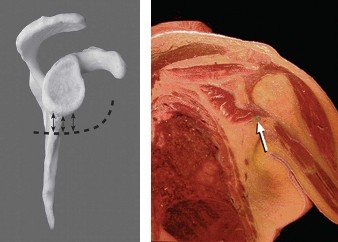

The correct answer is (C). This structure is a thickening of the coracohumeral ligament that starts anteriorly just posterior to the short head of the biceps tendon on the coracoid process, extends posteriorly through the edge of the avascular zone of the supraspinatus and infraspinatus, and ends at the inferior edge of the infraspinatus. One proposed function of the cable is to act like a cable in a suspension bridge, helping to evenly distribute forces on the humeral head produced by the rotator cuff (see Fig. 2–6).

Figure 2–6_Illustration showing the rotator cable and rotator crescent. B, rotator crescent; C, rotator cable; BT, biceps tendon; I, infraspinatus; S, supraspinatus; TM, teres minor. (Redrawn from Burkhart SS, Lo IKY. Arthroscopic rotator cuff repair. _J Am Acad Orthop Surg. 2006;14(6):333–346.)

The rotator crescent (Answer A) is the thin tissue that exists lateral to the rotator cable medial to the attachment of the supraspinatus and infraspinatus. It is composed on the tendons of these two rotator cuff muscles (see Fig. 2–6).